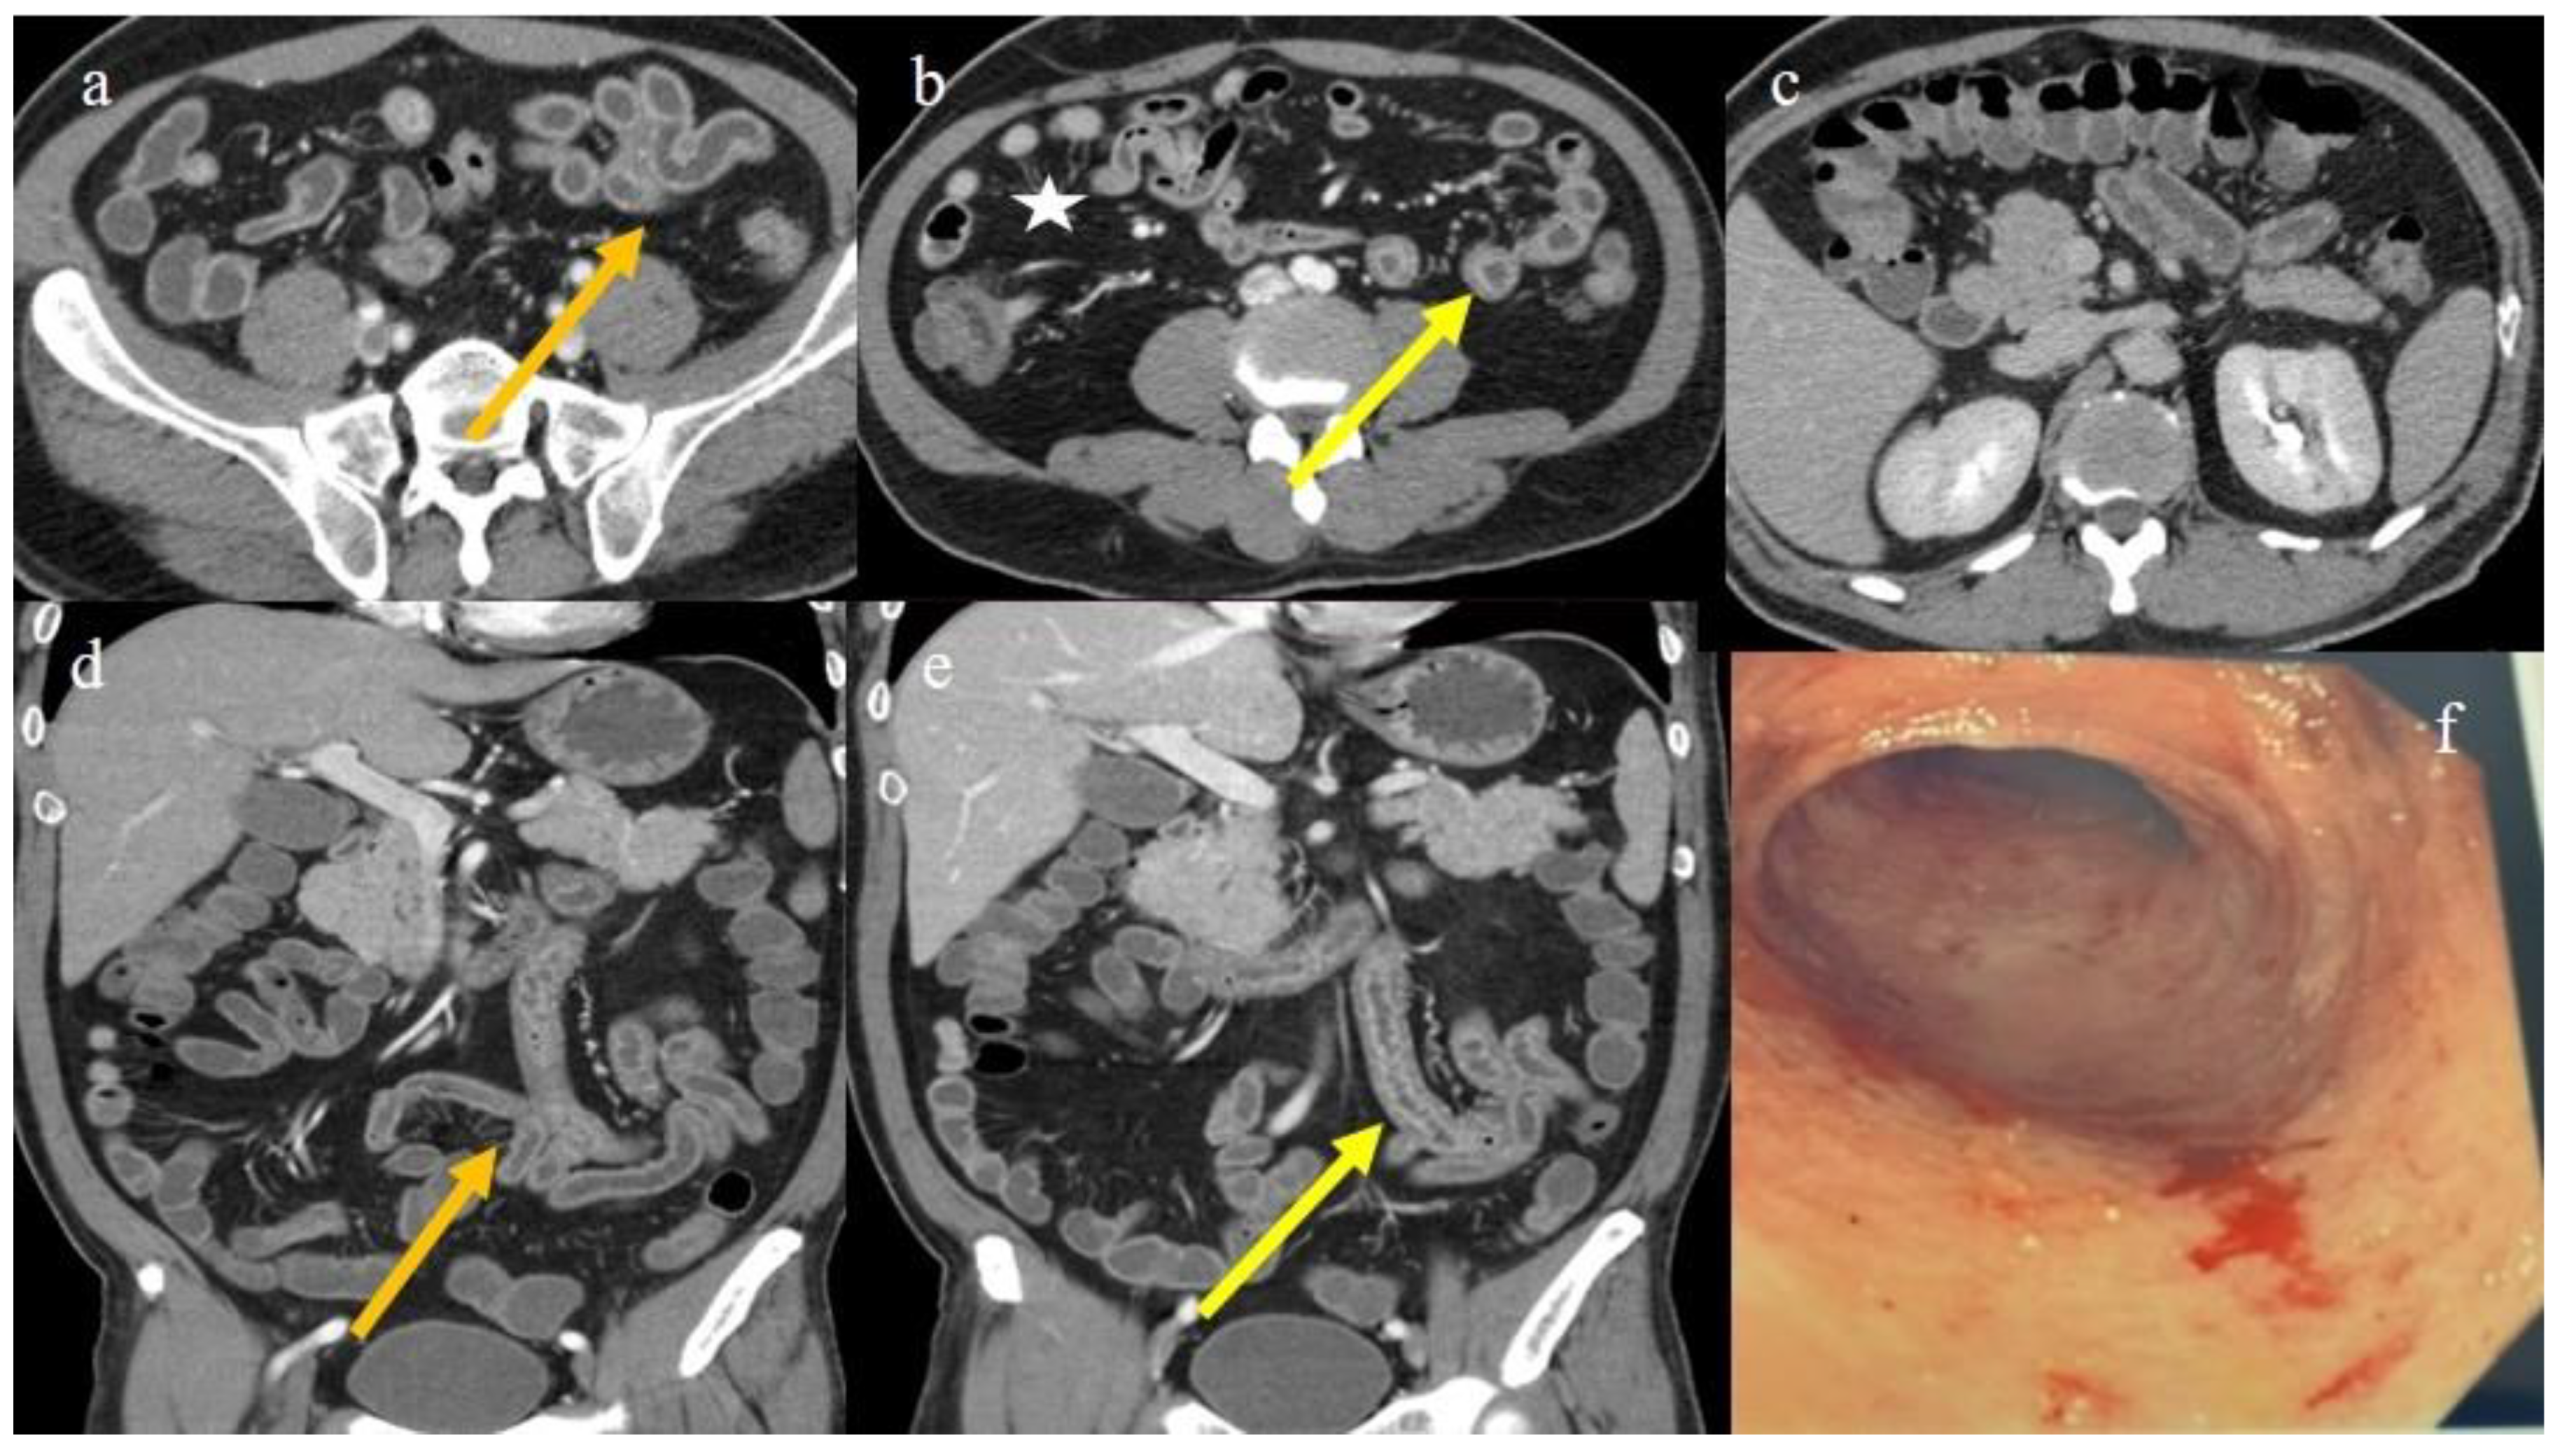

| 2 | P | P | Diffuse parietal thickness with stratified enhancement | Multisegmental thickness with homogeneous mucosal enhancement | Diffuse comb sign and poor reactive mesenteric lymph node | Mild gallbladder thickness and mild biliary tract dilatation |